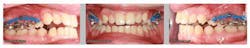

A healthy 15-year-old male presents to the clinic with an anterior open bite. His case is outlined in the figures below.

The patient in the above case report is still in active treatment. Now that successful maxillary posterior intrusion has been accomplished, the remaining full, fixed orthodontic appliances can be placed. The TPA can be removed and the molar intrusion will be held for the remainder of treatment with a ligature tie placed from the first molar to the TADs. The TADs will be kept in place for the remainder of treatment to maintain the stability of the intrusion as bone remodeling occurs.